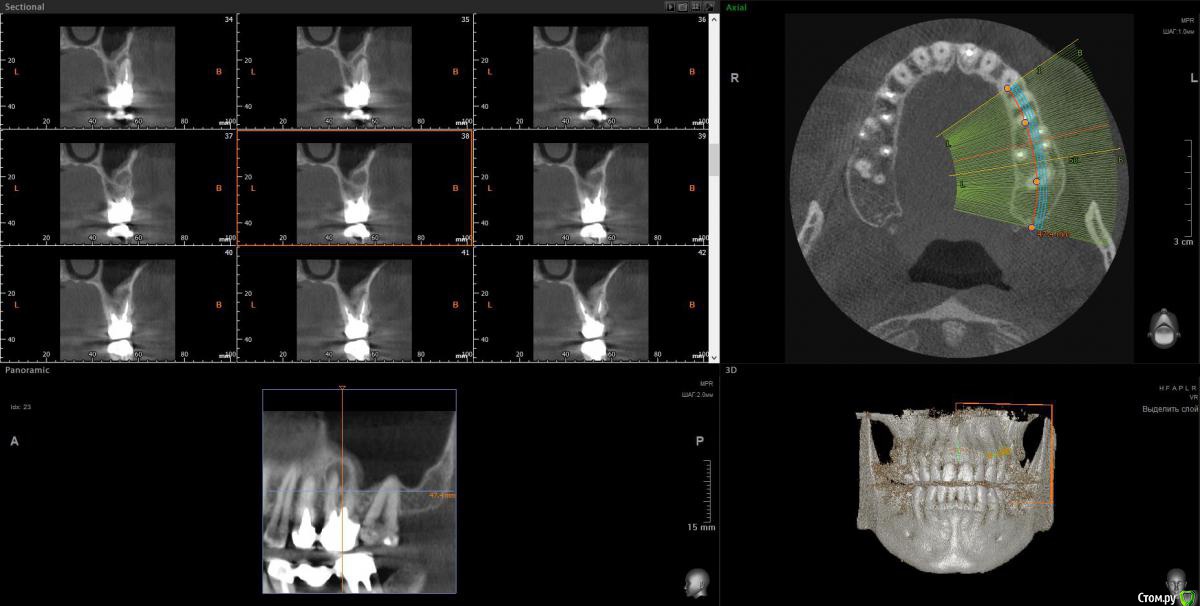

wladdX Опубликовано 12 февраля, 2018 Поделиться Опубликовано 12 февраля, 2018 Скрины 1 Ссылка на комментарий

Taurus007 Опубликовано 13 февраля, 2018 Автор Поделиться Опубликовано 13 февраля, 2018 wladdXОгромное спасибо за скриншоты. Я бы даже близко так не смог) Пришел расчет и анализ ТРГ. Заключение.pdf Ссылка на комментарий

Bier Опубликовано 22 февраля, 2018 Поделиться Опубликовано 22 февраля, 2018 Справа синуслифтинг не потребуется 100%Слева - возможно в области 26 зуба. Для оценки прикуса одного ТРГ мало, надо еще фото моделей. Вам их наверное делали? Ссылка на комментарий

Taurus007 Опубликовано 24 февраля, 2018 Автор Поделиться Опубликовано 24 февраля, 2018 Справа синуслифтинг не потребуется 100% Слева - возможно в области 26 зуба. А в целом, можно ли сейчас не трогать область, где возможно потребуется синуслифтинг, поскольку в практическом смысле это наименее проблемная область, хоть коронки и стоят уже 9 лет ? надо еще фото моделей. Вам их наверное делали? Не делали. Это как-то в домашних условиях возможно? Ссылка на комментарий